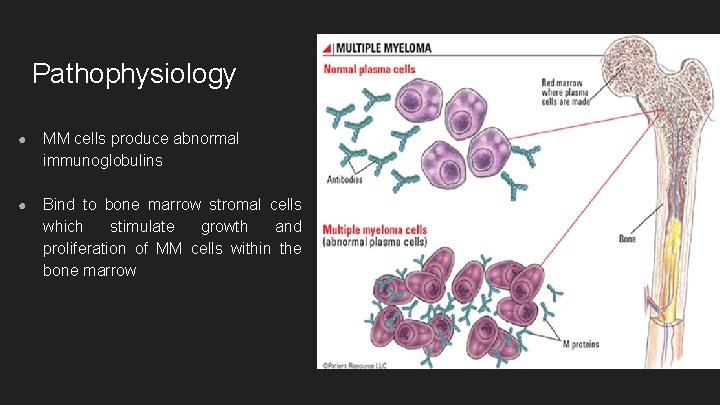

Pathophysiology ● MM cells produce abnormal immunoglobulins ● Bind to bone marrow stromal cells which stimulate growth and proliferation of MM cells within the bone marrow